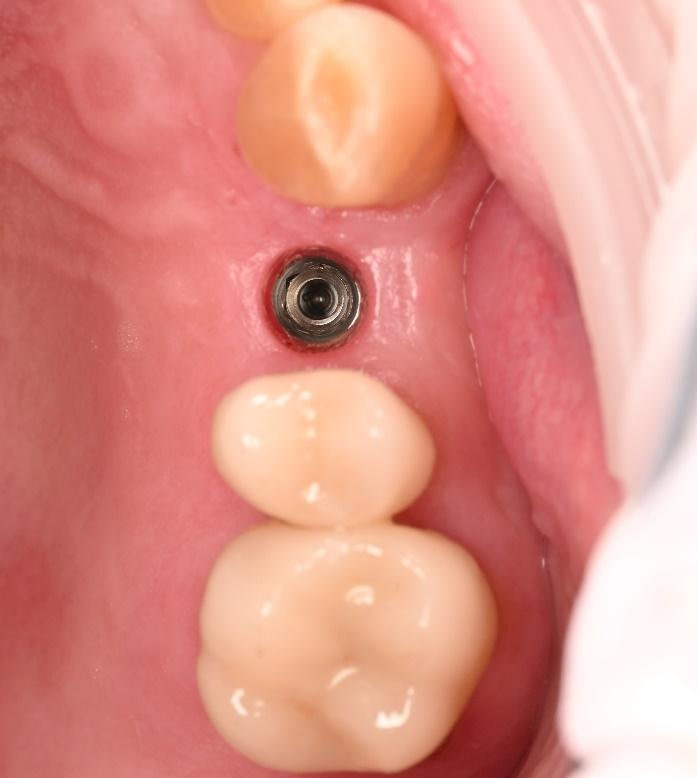

Three months after the implant surgery, a thorough post-operative assessment revealed excellent healing and implant stability.

Digital impressions were captured using the TRIOS 4 intraoral scanner, and the implant-supported crown was designed using 3Shape Design Studio.

Implant detection matches the scan body in the intraoral scan with the digital library. A colour scale is given to show the accuracy of the matching (Green is good).